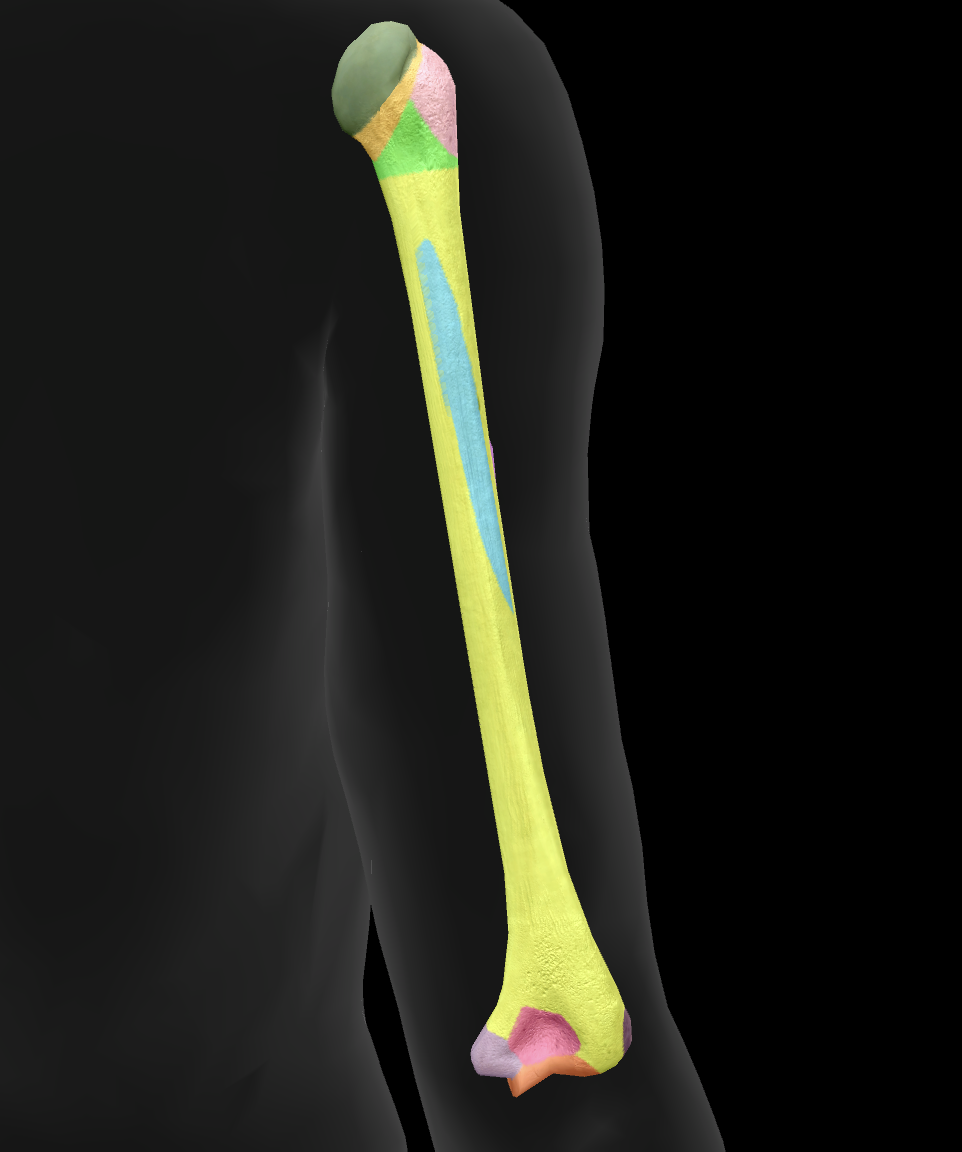

What bone is this?

humerus

What is this boney landmark?

head

What is this boney landmark?

anatomical neck

What is this boney landmark?

surgical neck

What is this boney landmark?

lesser tubercle

What is this boney landmark?

bicipital grove

What is this boney landmark?

deltoid tuberosity

What is this boney landmark?

shaft

What is this boney landmark?

capitulum

What is this boney landmark?

trochlea

What is this boney landmark?

radial fossa

What is this boney landmark?

coronoid fossa

What is this boney landmark?

medial epicondyle

What is this boney landmark?

lateral epicondyle

What is this boney landmark?

greater tubercle

What is this boney landmark?

radial grove

What is this boney landmark?

olecranon fossa

What is this boney landmark?

lateral supracondylar ridge

What is this boney landmark?

medial supracondylar ridge